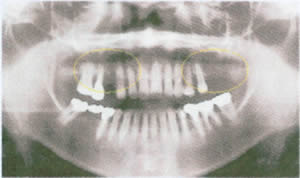

| 一般的治療なら右上4番欠損部にブリッジ 左上6・7番に部分末義歯を使用 |

インプラントを使用 | ||

![]() |

支持歯や鈎歯の寿命は極めて危うい |

残存歯を犠牲にしない |

喪失してしまうと、奥歯の咬合維持を失うので、前歯部も崩壊する |

咬合支持歯数が増加されるので、残存歯の負担が軽減される |